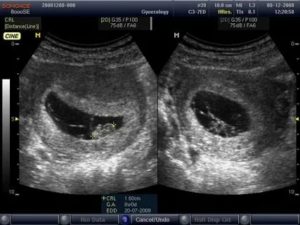

Пройти УЗИ рано или поздно придется любой, даже самой здоровой женщине, ведь эта методика — обязательный вариант обследования при беременности. С помощью 3D УЗИ аппарата можно увидеть в реальном времени своего малыша, рассмотреть ручки и ножки, увидеть его в движении и услышать биение сердца.

Что показывает УЗИ на первых сроках беременности

УЗИ при беременности выявляет:

- Наличие и характер беременности, срок, стартовые параметры развития. Очень важно не пропустить первое УЗИ на сроке 10-11 недель. Именно тогда по росту и весу ребёнка можно вычислить точную дату родов. Также эти данные помогут в дальнейшем следить за правильным развитием малыша. На более поздних сроках наблюдаются погрешности, мешающие установлению точного срока родоразрешения.